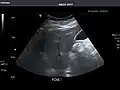

Liver

Ultrasonography of the liver with some standard measurements[6]

In patients with deranged liver function tests, ultrasound may show increased liver size (hepatomegaly), increased reflectiveness (which might, for example, indicate cholestasis), gallbladder or bile duct diseases, or a tumor in the liver.

Liver: Diffusely homogeneous and normal in echogenicity. No focal mass or contour nodularity. No intrahepatic biliary ductal dilatation.

Portal Vein: Patent main portal vein.

Gallbladder: No stones, wall thickening, or pericholecystic fluid.

Common Bile Duct: Nondilated measuring 1.3 mm at the level of the porta hepatis.